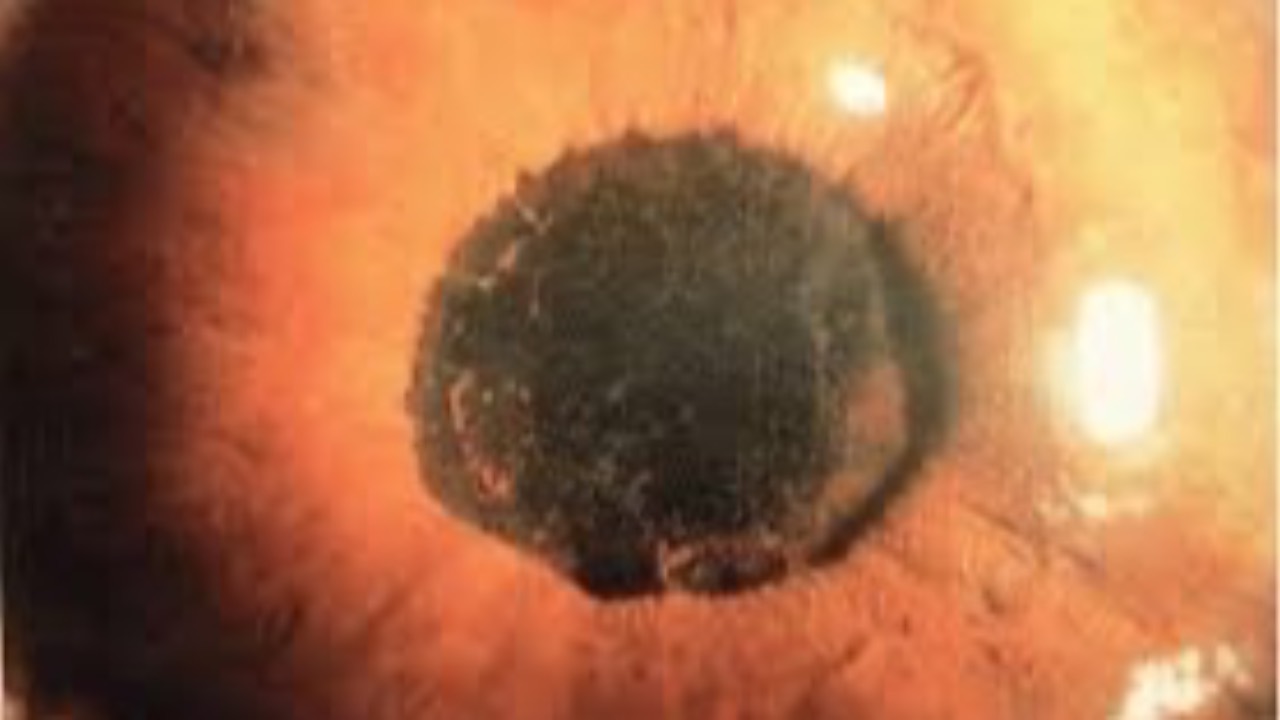

The Slit Lamp is Living Histopathology

A wonderful review...even if you're not a student!

Written by Paul A. R. Meyer, a very impressive review of the slit-lamp was recently published in Nature: Eye. Whether your a seasoned clinician or not, this is a fantastic article celebrating the instrument we use everyday.

The slit-lamp biomicr...